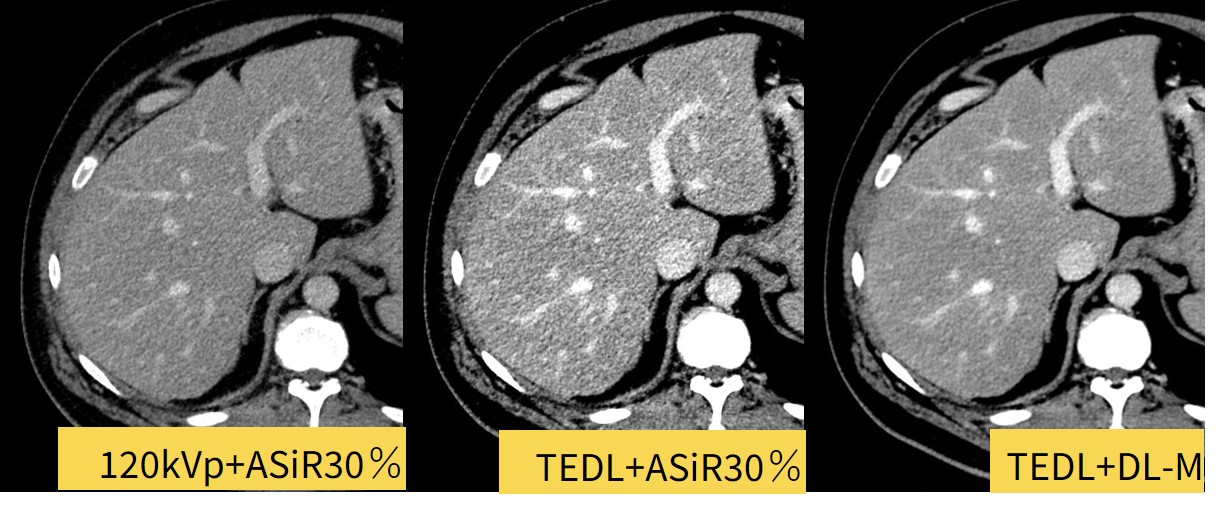

True Enhance DLの臨床使用について

True Enhance DLはAscend Eliteにのみ搭載されている機能で、通常CT検査で用いられる120kVpの取得データに加え50keV相当の低エネルギーの画像の再構成が可能となります。当院で使用しているversionからはTFDLとの併用も可能となりました。

現在当院では主に術前検査や腎機能障害があり造影剤を低減したいときや、副作用によって従来のタイミングで撮影出来なかった際にも使用しており、体格によってTFDLはmediumかhighを使用しています。

Fig4. TFDLとの併用でより使いやすくなったTEDL